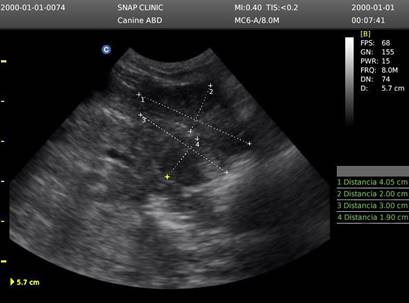

En la Figura 4 la evaluación ecográfica reveló una corteza renal hiperecogénica, sugiriendo un cuadro de LRA secundaria a la ingesta de AINEs. Ante este hallazgo, se procedió con el protocolo de emergencia, cuya primera medida fue la interrupción de la administración del fármaco. Posteriormente, la confirmación diagnóstica se obtuvo mediante analítica sanguínea (hemograma y bioquímica), lo que permitió personalizar la terapia de soporte y el manejo sintomático necesarios para la estabilización del paciente

Figura 4. Ecografía del riñón izquierdo (Se observa un ligero aumento de ecogenicidad a nivel de la corteza renal sugestivo de un proceso inflamatorio que está cursando el paciente). (INNOVAVET Riobamba -25 de abril de 2025) (Ecógrafo chison eco 3).